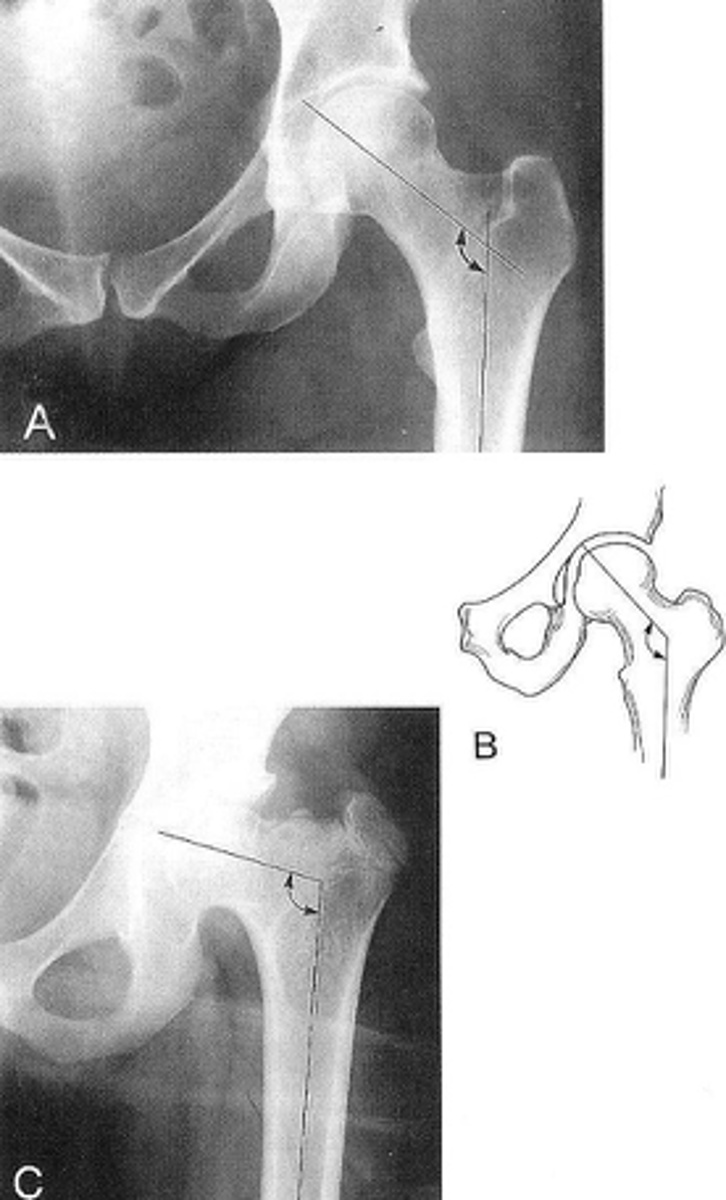

9

New cards

Right: gluteus medius

Left: gluteal fat stripe

ID 5

<p>ID 5</p>

10